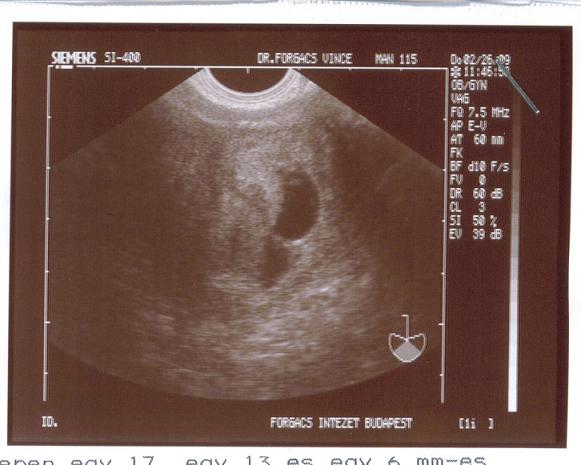

Nekem 2007. szeptemberében megcsinálták a HSG vizsgálatot, az jó lett, páromnak a sperma vizsgálat úgyszintén. Elvileg a hormonjaim is jók, leszámítva a prolaktint, arra meg kapom a napi 1 tbl. Bromocriptint. Hát ennyi...